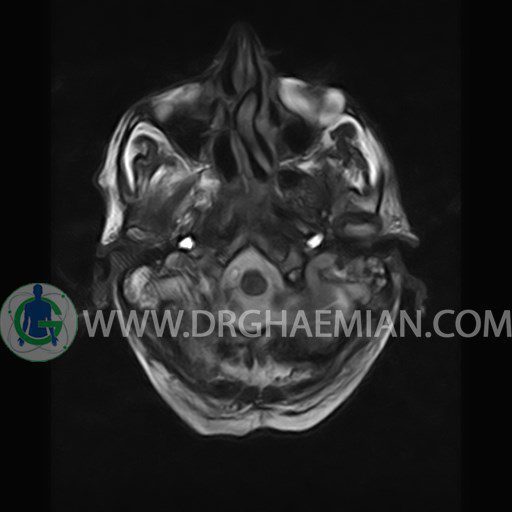

ام آر آی گوش (کانال شنوایی داخلی) یک روش تصویربرداری غیر مداخله ایی و بدون دردی است که با استفاده از امواج رادیویی و میدان مغنایسی قوی تصاویری با جزییات از کانل استخوانی که اعصاب و عروق خونی را از مغز به گوش داخلی می برد ایجاد می کند. در این کیس ماستوئیدیت سمت چپ دیده می شود.

INTERNAL AUDITORY CANAL MRI

(without contrast)

Technique: axial – coronal T1 , coronal T2 , Axial FLAIR .

The vestibulocochlear nerve on each side shows normal course and diameter .

The cochlea and semicircular canals appear normal .

– Hyperintensity in left transverse & sigmoid sinuses suggestive for venous stasis & thrombosis

– Fluid in left mastoidal cells suggestive for mastoiditis

are seen